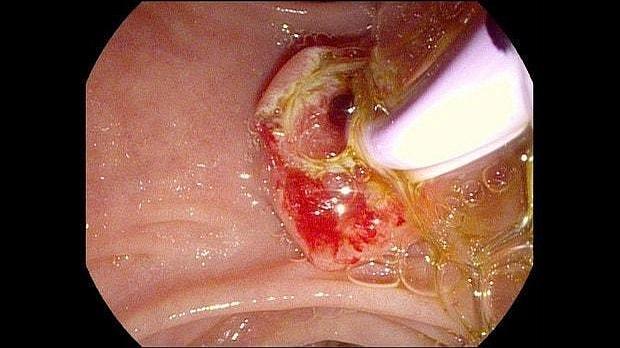

Здравствуйте. Пациентка, 32 года. Поступила на хирургическое отделение с диагнозом ЖКБ: холедохолитиаз. По данным МРТ: ЖКБ, множественные мелкие конкременты холедоха. При дуоденоскопии выявлено наличие вклиненного конкремента большого дуоденального сосочка. Выполнена прекатсфинктеротомия, получено 3 конкремента, диаметром около 0.4-0.5 см. Далее канюляция холедоха проволочным папиллотомом, выявлены многочисленные конкременты холедоха. Выполнена литоэкстракция ревизионным баллоном (на последнем фото окклюзионная холангиография - в просвете холедоха не конкременты, а пузырьки воздуха)).